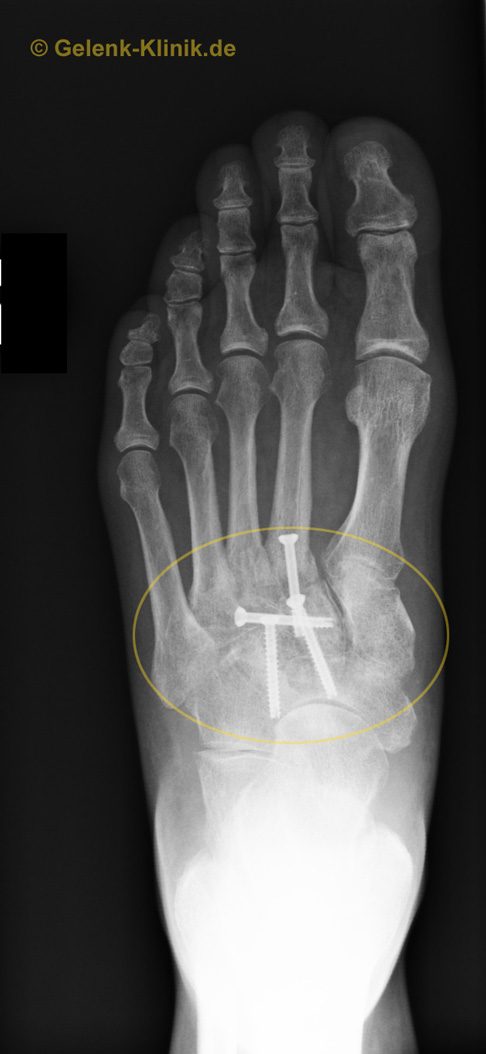

Das Röntgenbild zeigt den Zustand nach der Versteifung der Fußwurzelgelenke (gelbes Oval). Die Implantate heben die Beweglichkeit der Fußwurzelgelenke auf und ermöglichen ein stabiles Verwachsen (Arthrodese) dieser Gelenke. Die Versteifung stoppt die schmerzhaften entzündlichen Prozesse an den Gelenkflächen endgültig. Weil die Beweglichkeit der Fußwurzelknochen nicht im Vordergrund steht, ist diese Versteifung im Alltag ohne Funktionsverlust durchführbar. © Gelenk-Klinik

Abhängig von der Lage des tatsächlich geschädigten Fußwurzelgelenks führt der Operateur einen Hautschnitt am Fußrücken durch. Unter Röntgen überprüft er die Lokalisation und Übereinstimmung mit dem vorliegenden SPECT-CT. Die Restknorpelanteile werden entfernt. Der knorpelnahe Knochen wird angefrischt, um das Zusammenheilen der Knochen während der Arthrodese (Versteifung) zu verbessern. Knochensubstanz kann je nach Defektgröße zusätzlich angelagert werden. Unter intraoperativer Röntgenkontrolle wird dann ein stabilisierendes Metallimplantat eingebracht. Je nach Schadensgröße können das Schrauben, Klammern oder Platten sein. Das Ausmaß der Arthrodese ist abhängig von der Zahl der betroffenen Gelenke und der begleitenden Fehlstellung.